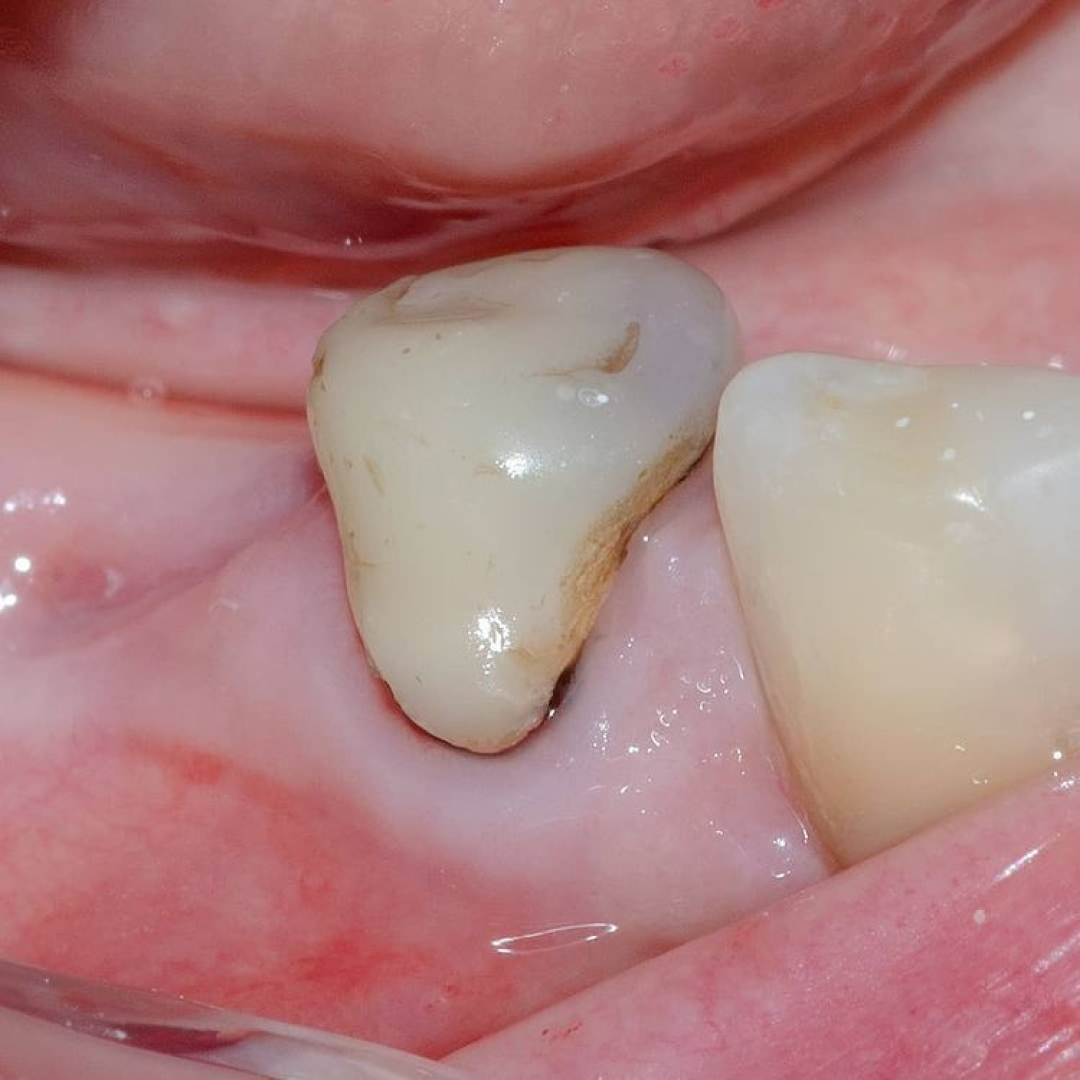

Повторное эндодонтическое лечение вторичного кариеса перед перекрытием зуба непрямой реставрацией 👍💙🎉